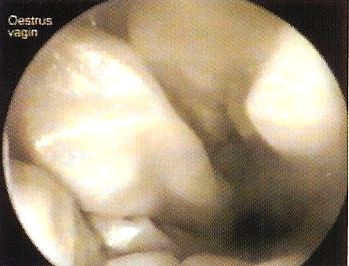

Vaginalendoskopie

Vaginalschleimhaut im Verlauf der Laufigkeit1Vaginalschleimhaut im Verlauf der Laufigkeit

Endoskopisches Erscheinungsbild der Vaginalschleimhaut. Im Verlauf der Läufigkeit bei der Hündin. Zu Beginn der Läufigkeit ist die Schleimhaut sehr ödematös (geschwollen), rötlich und glänzend (oben) später, zum Östrus hin, wird sie faltenreich und blass.